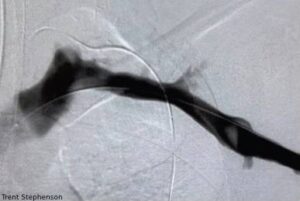

The patient was seen the next day in the vascular clinic where she had a repeat venous doppler that showed an acute deep vein thrombosis in the axillary subclavian vein. She then underwent a catheter directed thrombectomy that same afternoon. She was then scheduled to have her first rib removed in 2 weeks.